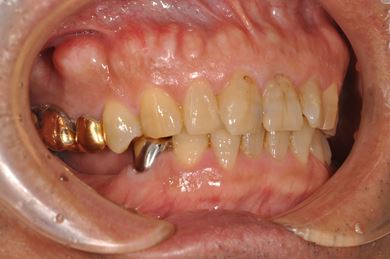

インプラント治療+セラミック治療

| 性別/年齢 | 男性 / 58歳 | ||||||||||||||||||||||||||||||||

| 主訴 | 部分入れ歯のバーが舌に当たるため、奥歯2本のインプラント治療を希望。 | ||||||||||||||||||||||||||||||||

| 治療方針 | 右下欠損部分をインプラント治療にて、機能的・審美的回復を行う。 | ||||||||||||||||||||||||||||||||

| 治療内容 | インプラント2本、メタルボンドセラミッククラウン8本、メタルボンドセラミック用土台6本 | ||||||||||||||||||||||||||||||||

| 総治療費 | 1,474,620円 | ||||||||||||||||||||||||||||||||

| 治療期間 | 1年6ヶ月 |